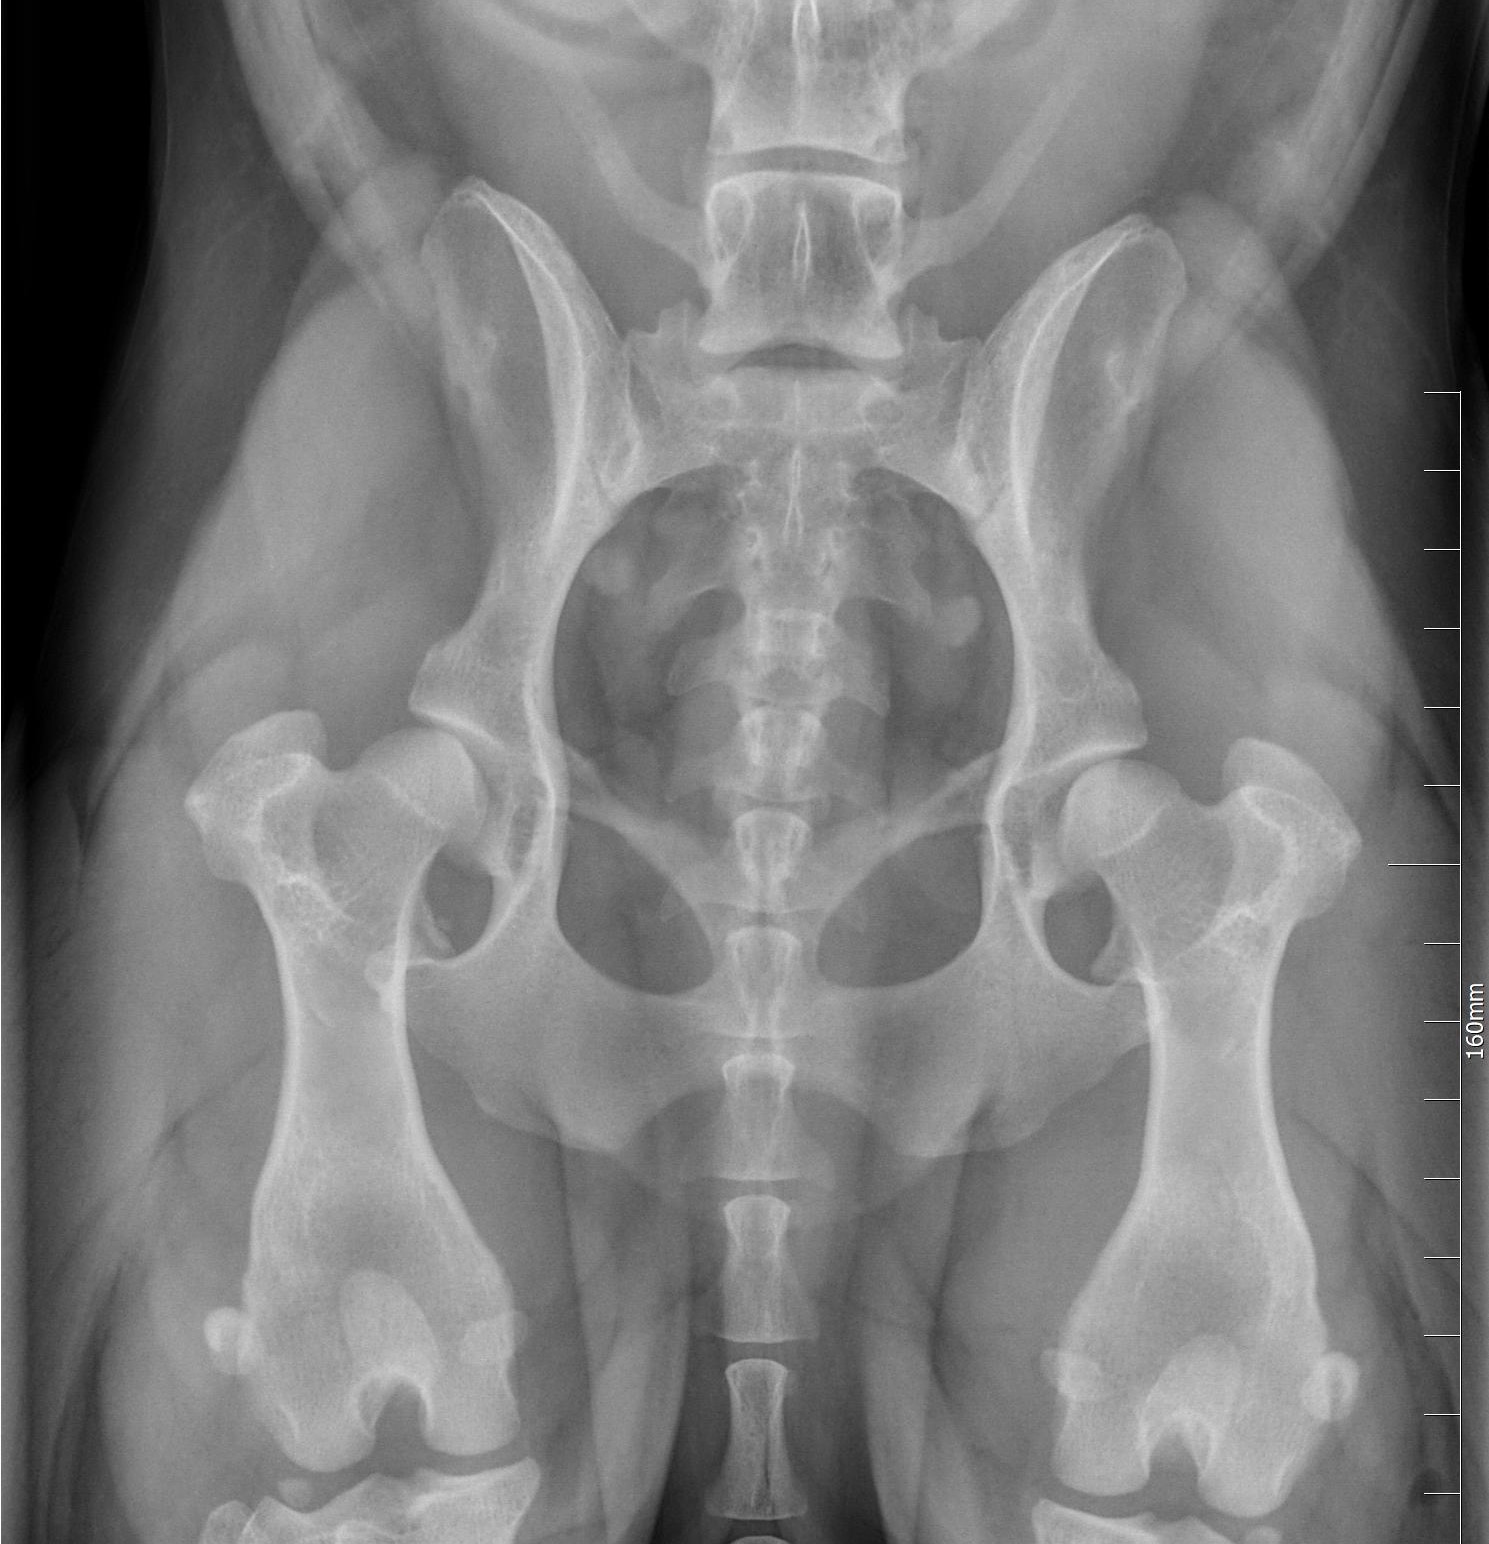

LONKKANIVELEN KASVUHÄIRIÖ

Lonkkanivelen kasvuhäiriö eli "lonkkavika", (engl. hip dysplasia, HD) on koirien yleisin luuston ja nivelten kasvuhäiriö. Se voidaan määritellä perinnölliseksi lonkkanivelen löysyydeksi. Lonkat ovat syntymähetkellä silmämääräisesti normaalit, mutta muutokset alkavat jo pennun ensimmäisten elinviikkojen aikana.

Löysyys lonkkanivelessä johtaa reisiluun pään ja lonkkamaljan riittämättömään kontaktiin. Alueelle kohdistuu epänormaalin suuri paine, joka on sitä suurempi mitä pienempi kontaktialue on. Tämä voi johtaa mikromurtumiin ja lonkkamaljan mataloitumiseen. Noin vuoden iässä lantion luutuminen on täydellistä ja yleensä kipukin helpottaa tässä iässä.

Lonkkanivelen kasvuhäiriö johtaa usein nivelrikkoon. Nivelrikon kehittymisen aikatauluun ja tyyppiin vaikuttavat rotukohtaiset ja yksilölliset erot. Lonkkanivelen kasvuhäiriön perimmäistä syytä ei tiedetä, mutta se periytyy tämänhetkisen tutkimustiedon perusteella kvantitatiivisesti eli siihen vaikuttaa useita eri geenejä. Myös ympäristöllä on vaikutusta lonkkavian ilmenemiseen ja vaikeusasteeseen.

Corgeilla on lonkkanivelen kasvuhäiriöitä lievästä - vaikea asteiseen. Ylipaino vain pahentaa oireita ja tämä on yksi niistä syistä, miksi cardigania ei tule päästää liian lihavaan kuntoon!

(Lähde: SWCS ry:n sivuilta, /www.corgiseura.net/terveys/rodussa-esiintyvat-sairaudet-ja-viat/lonkkaniveldysplasia/)